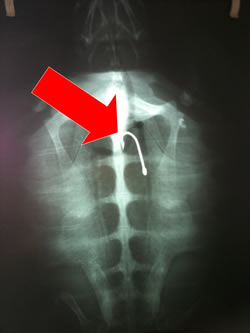

Αφού του χορηγήθηκε ορός και αντιβιοτικά, οδηγήθηκε λίγες ημέρες αργότερα σε διαγνωστικό κέντρο της περιοχής για ακτινογραφίες, με τις οποίες επιβεβαιώθηκε η παρουσία αγκιστριού αρκετά βαθιά στο στομάχι.

Κατόπιν συνεννόησης με την κτηνίατρό μας, πρόκειται να προγραμματιστεί η επεμβατική της διαδικασία.